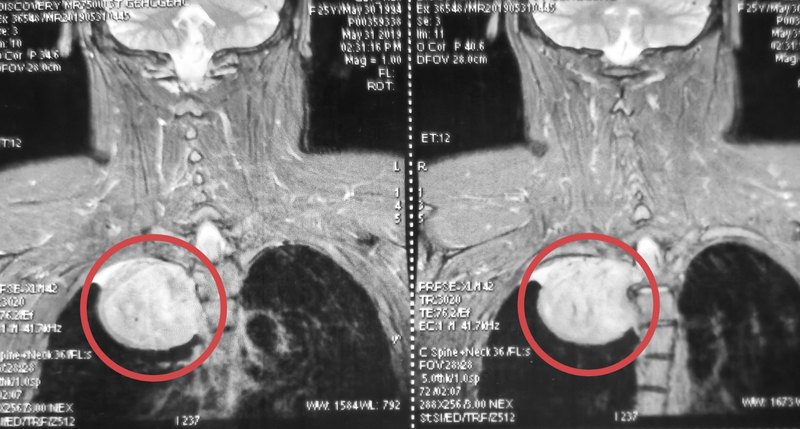

日常生活中,頭痛頭暈是許多人都出現(xiàn)過的癥狀,那么大家會如何處理呢?今年32歲的李先生,也發(fā)生了頭痛頭暈的癥狀。由于發(fā)病突然,頭暈發(fā)作時還伴有行走不穩(wěn)的情況,幾次發(fā)作之后,李先生便前往當?shù)蒯t(yī)院進行治療。經(jīng)過顱腦CT平掃和DSA腦血管造影檢查,結果提示:李先生可能出現(xiàn)了蛛網(wǎng)膜下腔出血的情況,但好在腦實質內沒有出血。而在顱腦右側橫竇乙狀竇區(qū),醫(yī)生卻發(fā)現(xiàn)了異常情況,于是做出了初步診斷:硬腦膜動靜脈瘺。不久,李先生在全麻下接受了硬腦膜動靜脈瘺栓塞術。不過,由于微導管位置不到位,這次介入手術失敗了。為尋求進一步治療,李先生慕名來到上海長征醫(yī)院神經(jīng)外科呂立權教授門診。在進行頭顱MRI平掃+增強檢查后,呂教授在患者的腦右側橫竇乙狀竇區(qū)發(fā)現(xiàn)異常信號,T1WI呈等低混雜信號,T2W2呈高低混雜信號,T1增強呈不均勻強化,周圍腦組織無明顯水腫。MRV檢查提示,患者的右側橫竇乙狀竇完全閉塞,右側頸靜脈未顯影。呂教授詳細分析了李先生的MRI影像學特征,并結合在外院做的DSA檢查結果,認為該患者的診斷不是硬腦膜動靜脈瘺,很可能是右側橫竇乙狀竇區(qū)腦膜瘤。腫瘤位置特殊,位于靜脈竇內,要完整切除腫瘤,需要行開顱手術。右側橫竇乙狀竇區(qū)異常信號,T1WI呈等低混雜信號,T2W2呈高低混雜信,T1增強呈不均勻強化,周圍腦組織無水腫。MRV檢查,右側橫竇乙狀竇閉塞,右側頸靜脈未顯影。手術過程中發(fā)現(xiàn),病灶位于右側橫竇乙狀竇內,竇內充盈飽滿,實性變,無正常引流功能。腫瘤起源于竇內壁,與內壁粘連緊密,無法完全分離。腫瘤血供豐富,質地較韌,部分囊變,囊液呈清亮黃色。于腫瘤與正常橫竇交界處結扎橫竇,在腫瘤遠端靠近頸靜脈球處結扎乙狀竇遠端,將腫瘤連同橫竇乙狀竇一并切除。術后MRI顯示:腫瘤切除滿意,周圍腦組織無出血壞死表現(xiàn)。術后MRI顯示右側橫竇乙狀竇區(qū)腫瘤切除滿意,臨近腦組織無出血壞死。術后病理結果回報顯示:腫瘤組織呈彌漫交織狀排列,瘤細胞呈梭形、卵圓形,胞漿較豐富,核深染輕度核異形,偶見核分裂,未見腫瘤性壞死,間質小血管部分呈分支狀擴張。病理結果考慮為:孤立性纖維性腫瘤(SFTI級)。A.HE染色可見梭形細胞B.信號轉導和轉錄激活因子6(STAT6)陽性。CCD34陽性;D“鹿角”型血管。什么是孤立性纖維性腫瘤?李先生患的是什么病呢?孤立性纖維性腫瘤(SFT)最早于1931年報道于世。一般多發(fā)生于胸膜腔或者全身其他部位,非常罕見的發(fā)生于顱內。近年來研究發(fā)現(xiàn),顱內孤立性纖維瘤(ISFT)和血管周細胞瘤(HPC)在基因表達上有相似性,于是2016年WHO中樞神經(jīng)系統(tǒng)腫瘤分類中便將SFT及HPC合并為同一類腫瘤,即:SFT/HPC。分析顯示,孤立性纖維瘤(SFT)好發(fā)于38-45周歲的中青年人群,且好發(fā)于男性。據(jù)文獻報道,SFT的年發(fā)生率約為0.2/10萬人,而SFT/HPC的發(fā)病率占顱內腫瘤的1.9-4%,發(fā)病率相當罕見。ISFT的發(fā)病位置通常位于與硬腦膜毗鄰的大腦鐮、大腦凸面、小腦幕、后顱窩和橋小腦角區(qū),腦室、鞍區(qū)和海綿竇區(qū)少見。李先生的發(fā)病位置位于橫竇乙狀竇區(qū),呈現(xiàn)為竇內生長,未突破竇腔。這在國內外都未見有相關報道,屬于罕見病例。那么ISFT具有哪些特點呢?據(jù)呂教授介紹,ISFT具有腦外腫瘤的特點,患者可以表現(xiàn)出頭痛、頭暈的癥狀。但是ISFT被纖維包膜包裹,與周圍腦組織之間有較為清晰的邊界,但多與硬腦膜或顱板以窄基底相連,所以很少發(fā)生“硬腦膜尾征”。發(fā)生ISFT該怎么辦?呂教授介紹,ISFT并沒有特殊的臨床癥狀,而且影像學特征與腦膜瘤非常相似,所以最重要的是鑒別。一般來說,ISFT在T1WI上以等信號或等低信號為主,而T2WI的信號則變化多樣,包括高信號、略高信號和低信號區(qū)。高信號主要對應腫瘤內部出血、囊變、壞死或相對新鮮的纖維化區(qū),略高信號反映腫瘤細胞密集區(qū),低信號區(qū)則反映富含膠原纖維區(qū),且膠原成分越多T2信號越低。與ISFT相比,腦膜瘤T1WI多為低至等信號,T2WI多為高至低信號,強化較均勻,且強化程度低于ISFT,“腦膜尾征”多見,瘤周水腫也較ISFT明顯。進一步的確診需要進行病理診斷,免疫組織化學方法中,STAT6、ALDH1和CD34是區(qū)分ISFT和腦膜瘤的最為重要的標志物。在治療方面,手術切除仍然是主要的治療方式,原則上盡量根治性切除以防止腫瘤復發(fā)和轉移,且腫瘤全切除的治療效果明顯優(yōu)于次全切除,術后復發(fā)率顯著降低。術后是否放療目前仍然有爭議,但是大部分證據(jù)顯示,術后放療可以提高治療效果,但是不能預防局部轉移或遠處轉移。如何預防復發(fā)?呂教授認為,ISFT的預后與以下因素相關:腫瘤大小和切除范圍,例如直徑>10cm或者未能完全切除便是不利因素;非典型或惡性腫瘤復發(fā)可能性高;CD34陰性病人預后差。綜合來看,呂教授建議李先生定期隨訪,而且要堅持長期隨訪,以避免復發(fā)或轉移風險。